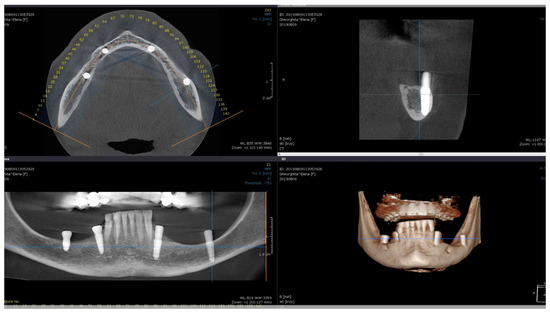

Direct visual access to the residual bone was obtained by elevating a full muco-periosteal flap. A lance drill was used to mark the implant site at approximately 2 mm towards the midcrest with respect to the buccal or lingual cortex. To avoid thermal osteonecrosis, copious cooling irrigation, new drills, and a maximum speed of 800 RPM were used for implant site preparation. After the osteotomy site was marked, a pilot 2 mm drill was selected to perform the preparation for the length of the selected implant. In-and-out manoeuvres were performed in order to facilitate cooling of the drills. If the implant is planned to be placed buccally, the drill must be oriented with the apex faced towards buccal wall, trying to keep the axis of the drill parallel to the buccal cortex. In most of the cases, if the pilot drill direction was properly assessed, minimal or even no bleeding will be observed and the patient will indicate no pain. If the osteotomy preparation was performed buccally, a bone dehiscence might be present. In this scenario, the following drills must be slightly pressed towards the inner wall (wall facing towards the middle of the alveolar crest) of the osteotomy site. This manoeuvre is performed by a digital propelling force on the head of the handpiece, according to the preparation protocol for D1 bone recommended by the implant company. If a 4.0 mm diameter tapered implant (AnyRidge, Megagen Implant Co., Daegu, Republic of Korea) is planned to be used, the following drills were selected for convenient site preparation: 2.7 mm, 3.3 mm, 3.8 mm for the whole length of the osteotomy and a 4.3 mm drill was used only for countersink. Implant insertion was done with the surgical motor (at 35 RPM). A similar drilling protocol is applied for 3.5 mm diameter implants (last drill 3.3 mm and 3.8 mm countersink) and a 4.3 mm drill for the whole length, for 4.5 mm diameter implants. Depending on the thickness of the surrounding soft tissues and the relation with the buccal mucosa, either a 7 mm long healing abutment (I-Gen Kit, Megagen, Daegu, Republic of Korea) or a customized healing abutment was connected to the implant, with digital clockwise rotations. Double layer suture (horizontal mattress and simple suture) was done with 5/0 resorbable suture (Vicryl, Ethicon, New Brunswick, NJ, USA). Patients were prescribed antibiotics (Augmentin®—amoxicillin plus clavulanic acid 1 g/every 12 h) and one tablet of anti-inflammatory drug (Ibuprofen 600 mg at every 8 h) for the following 5 days. Patients were instructed to avoid brushing the neighbouring teeth in the treated area and chlorhexidine solution (0.12%) was prescribed for daily usage (twice a day for 1 min). Sutures were removed after 14 days [16]. All patients were recalled for clinical checkup 1 day, 1 week, 2 weeks, and 2, 6, 12, 24, and 36 months after surgery. All complications, both during the surgery and postoperative, were reviewed. A postoperative CBCT was done to assess implant positioning. Buccally tilted and lingually tilted implant positioning are presented in Figure 1 and Figure 2, respectively.

Figure 2.

Postoperative CBCT of patient no. 5: (Upper left)—axial view of the mandible; (upper right)—sagittal left view of the lingually tilted implant (36); (lower left)—coronal view of the mandible; (lower right)—3D view of the mandible.